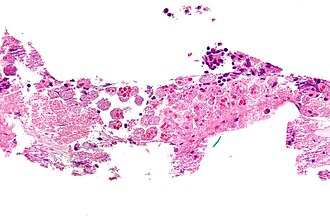

Amebiasis. H&E stain. | |

Microscopic

Features:

- Entamoeba histolytica are round/ovoid eosinophilic bodies ~ 40-60 micrometers in maximal dimension.

- Found in bowel lumen.

- Ingest RBCs.